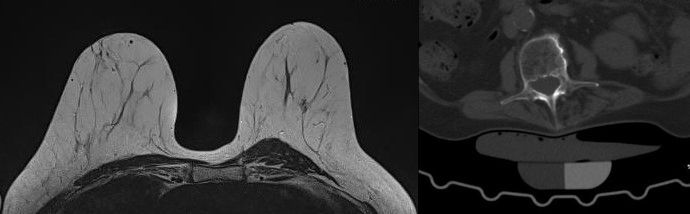

MR-Mammographie

Die Magnetresonanz-Mammographie, kurz MR-Mammographie, ist eine fortschrittliche Bildgebungstechnologie, die in der radiologischen Diagnostik eingesetzt wird, um eine detaillierte und präzise Darstellung des Brustgewebes zu ermöglichen. Dieses Verfahren spielt eine entscheidende Rolle bei der frühzeitigen Erkennung von Brustveränderungen, auch in Fällen, in denen herkömmliche Mammographie oder Ultraschall möglicherweise nicht ausreichend sind. Im Gegensatz zur Röntgenmammographie kommt die MR-Mammographie ohne Röntgenstrahlung aus, was sie zu einer sicheren Option für wiederholte Untersuchungen macht. Für Frauen mit dichtem Brustgewebe, bei denen herkömmliche Mammographien herausfordernder sein können, bietet die MR-Mammographie eine verbesserte Bildqualität und Aussagekraft. Deshalb wird sie von der Europäischen Gesellschaft für Brustbildgebung (EUSOBI) in diesen Fällen sogar im Rahmen der Vorsorge anstatt der konventionellen Mammographie empfohlen.